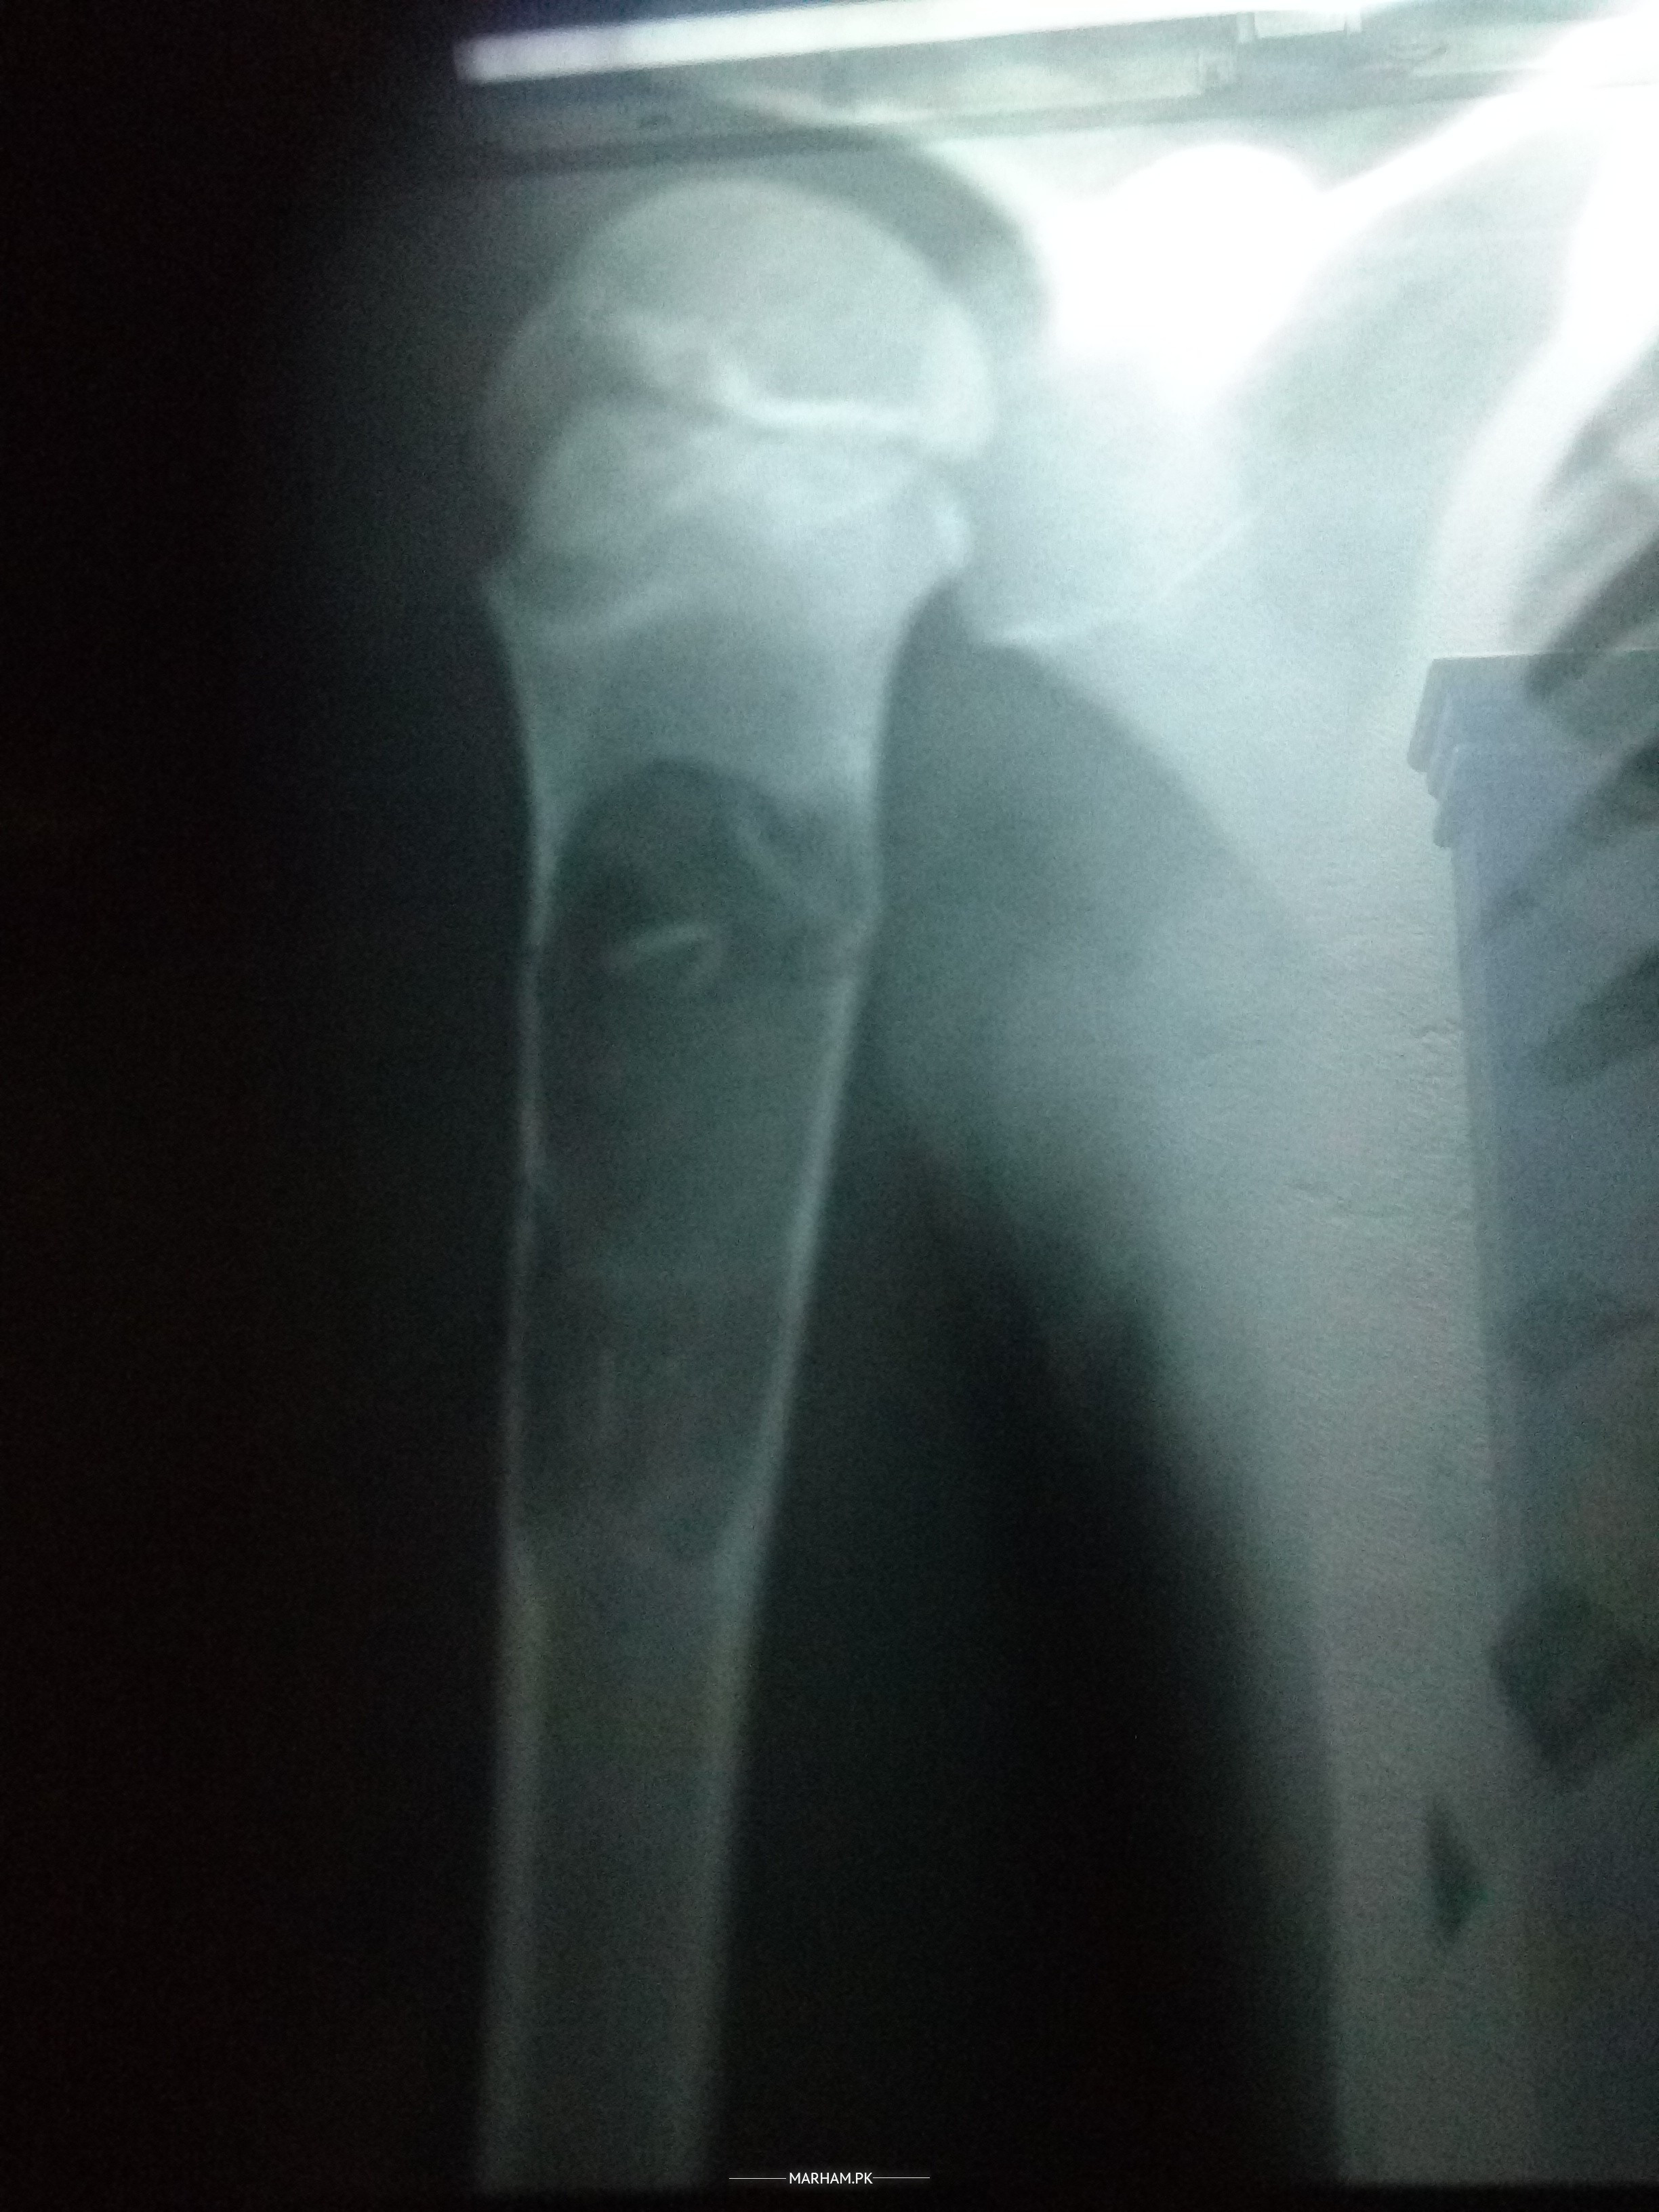

Asking For Self, Male, 6 year years old, Lahore

Hello dear Dr. I am Aamir from Pakistan city Lahore. Dr. My son mueez Aamir diagnosed unicameral bone cyst. One Dr. Recommended surgery & bone graphting And two Dr. Recommended steroid injection. Some 15 days later 160ml steroid inj in bone injected. Dr, plz tell me How many days or month bone properly heal. And this what good treatment steroid inj.

Yes inj is fine it may take 3 months to heal, u can send me x ray for further opinion

It is the treatment of choice and it takes up to year.

X-ray mueez Aamir

both treatments r recomanded . it takes few months to be a nornal bone